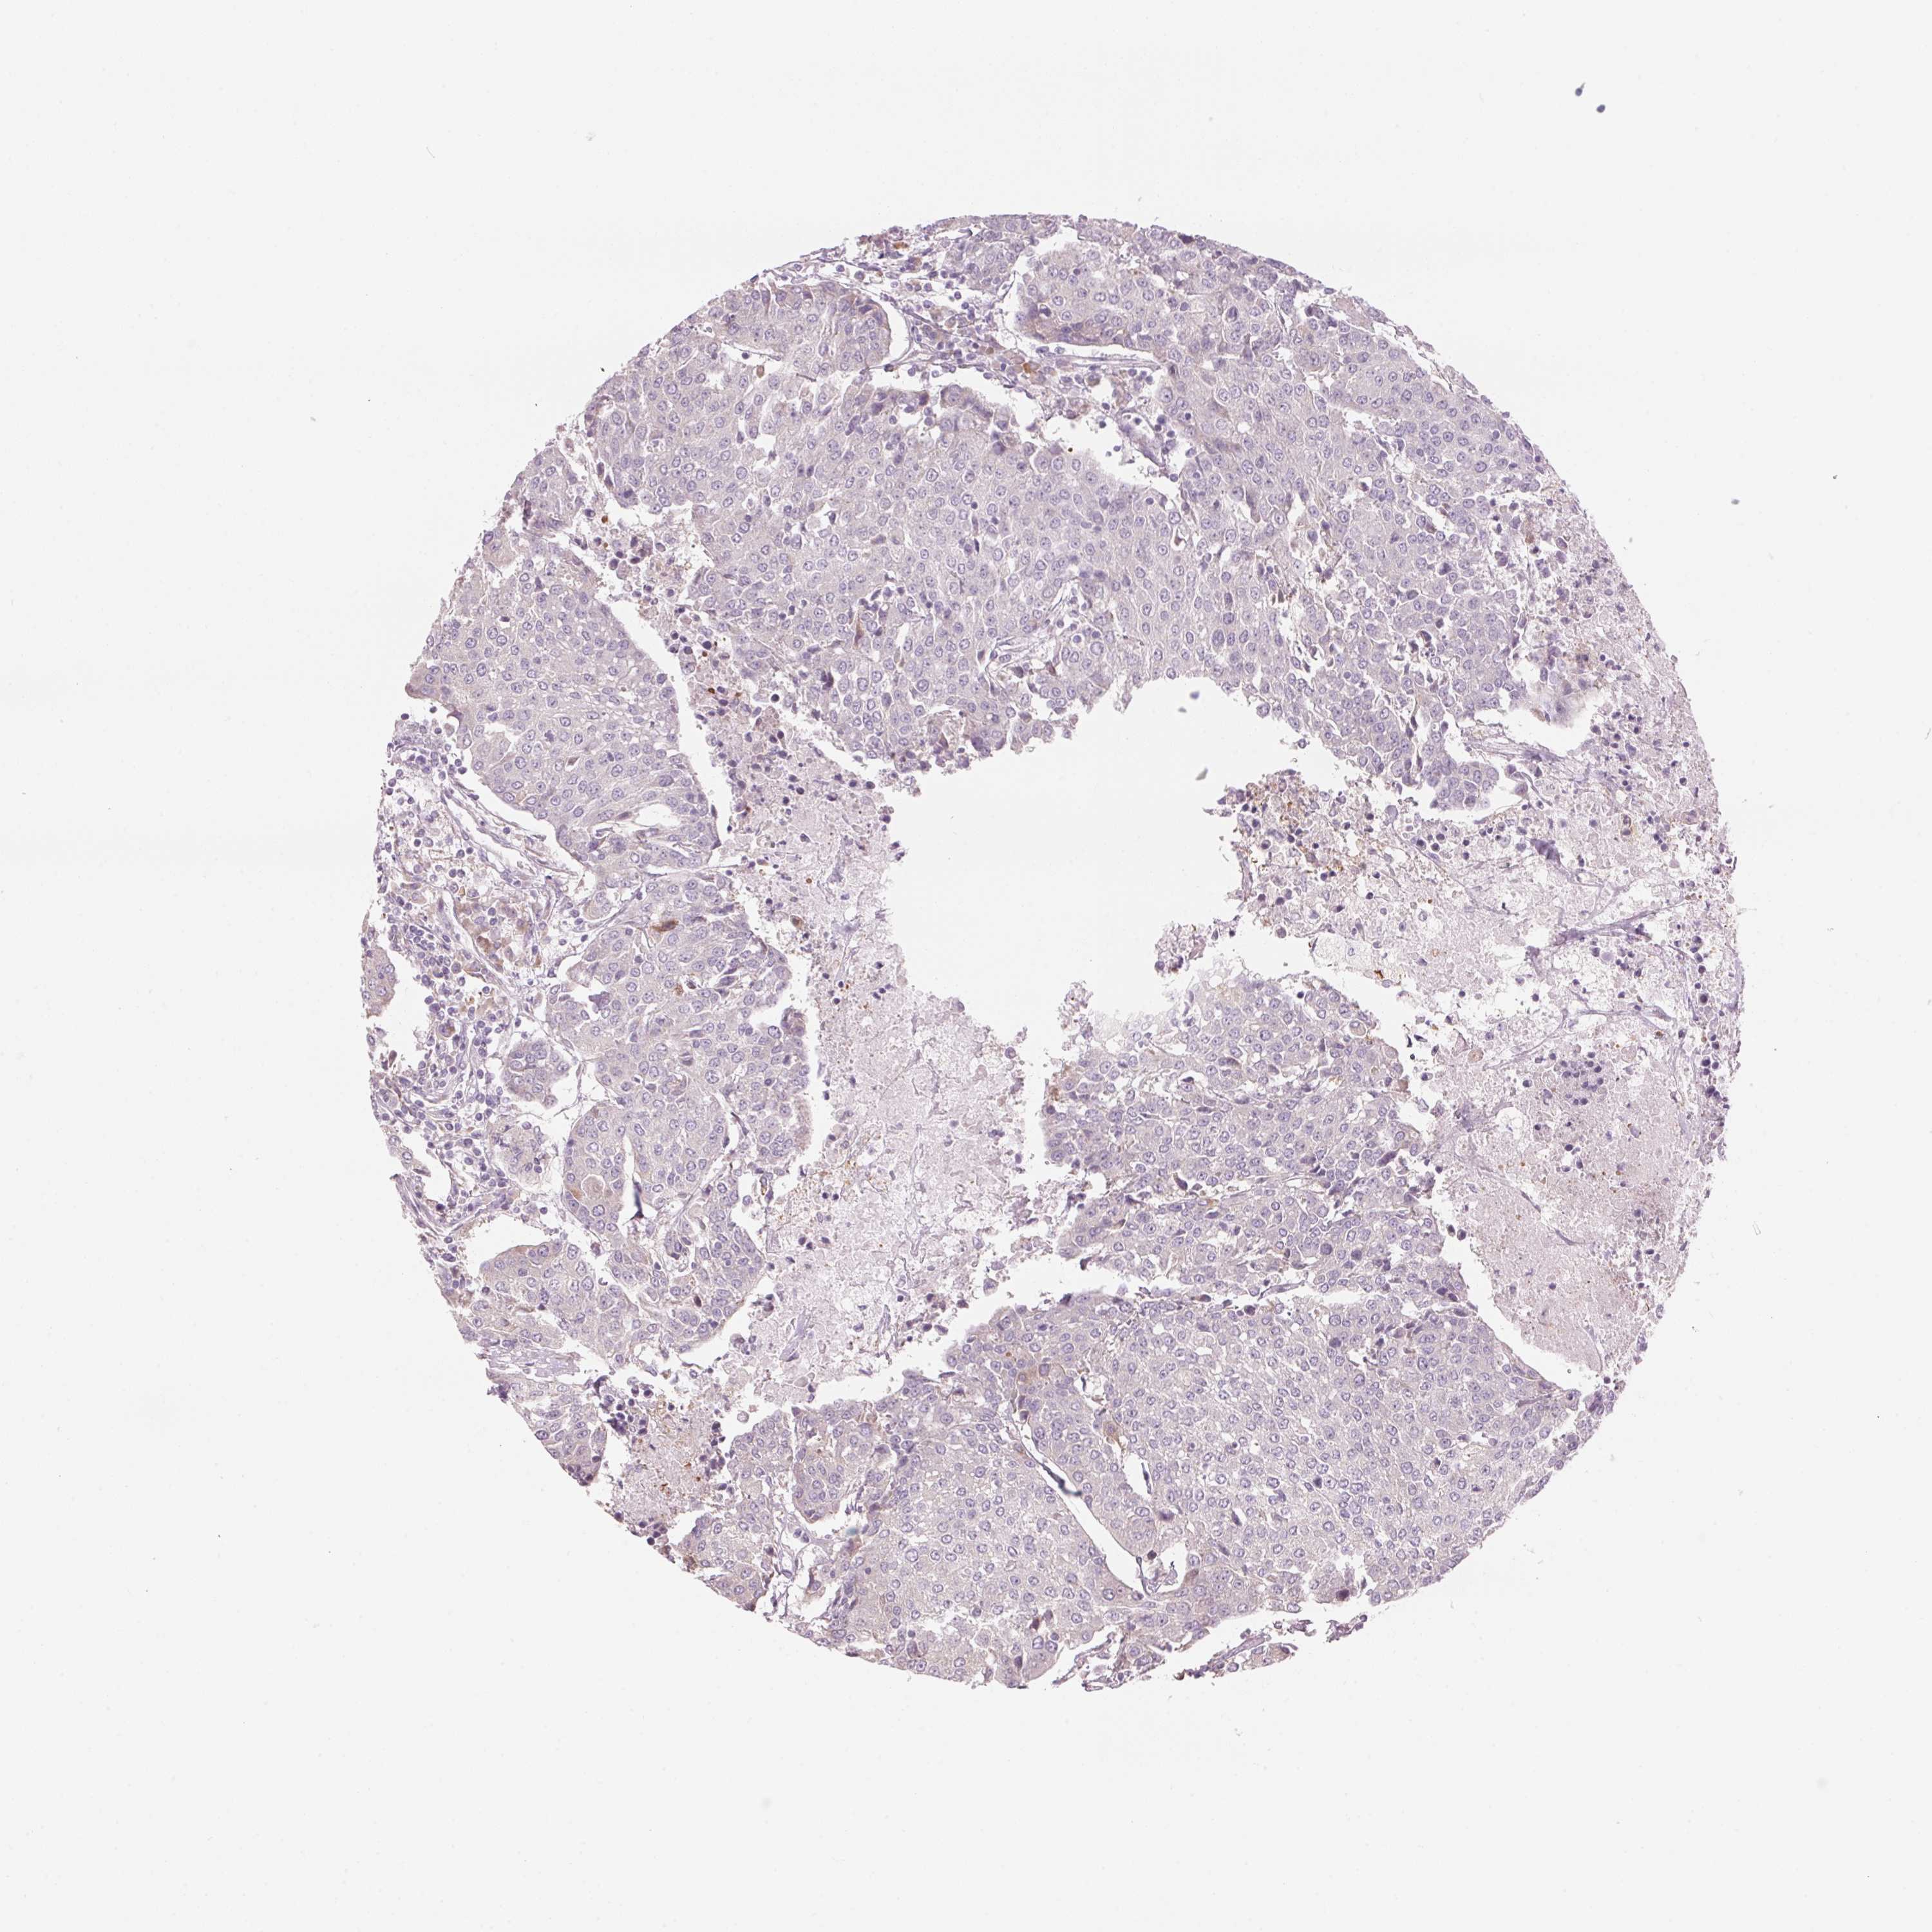

UROTHELIAL CANCER - Protein expressioni

A mouse-over function shows sample information and annotation data. Click on an image to view it in a full screen mode. Samples can be filtered based on level of antibody staining by selecting one or several of the following categories: high, medium, low and not detected. The assay and annotation is described here.

Note that samples used for immunohistochemistry by the Human Protein Atlas do not correspond to samples in the TCGA dataset.

Antibody stainingi

Antibody staining in the annotated cell types in the current human tissue is reported as not detected, low, medium, or high, based on conventional immunohistochemistry profiling in selected tissues. This score is based on the combination of the staining intensity and fraction of stained cells.

Each image is clickable and will lead to virtual microscopy that enables deeper exploration of all samples and also displays staining intensity scores, fraction scores and subcellular localization as well as patient and tissue information for each sample.

Antibody HPA027501

Staining

High

Medium

Low

Not detected

Intensity

Strong

Moderate

Weak

Negative

Quantity

>75%

75%-25%

<25%

None

Location

Nuclear

Cytoplasmic/membranous

Cytoplasmic/membranous,nuclear

Urothelial carcinoma, High grade

Urothelial carcinoma, Low grade